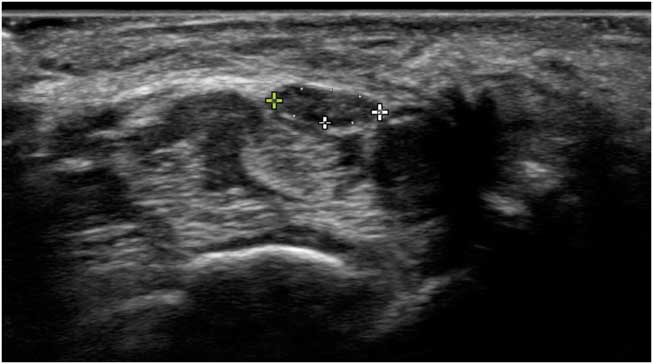

Ultrasound imaging is based on reflections that are created when the ultrasound beam encounters a transition between tissues with different sound velocities and gets reflected back to the transducer. Normal human muscle tissue has relatively few such transitions, which provides a relatively black appearance on the screen. In transverse images, this has been dubbed a “starry night” appearance: a black night sky (the muscle fiber tissue) with speckles that look like stars (the fascia structures; Figure 1A). Longitudinally, the muscle fascicle architecture become visible, which shows as a linear (Figure 1B), bi-pennate or triangular structure in the ultrasound image. Normal peripheral nerves look like round, oval, flat or triangular structures with a white edge (the epineurial rim), filled with black dots of varying sizes (the nerve fascicles; Figure 2A). In a longitudinal view they look like a set of railroad tracks (Figure 2B).

Figure 2 (A) Shows a transverse image of the median nerve in the forearm. The hyperechoic rim of the epineurium and the internal fascicle bundles are clearly visible. (B) Shows a longitudinal image of the median nerve in the forearm. The markers delineate the outer epineurial edge of the nerve; internally, the longitudinal lines of perineurial fascia are seen. The nerve as a whole resembles a set of railway tracks.